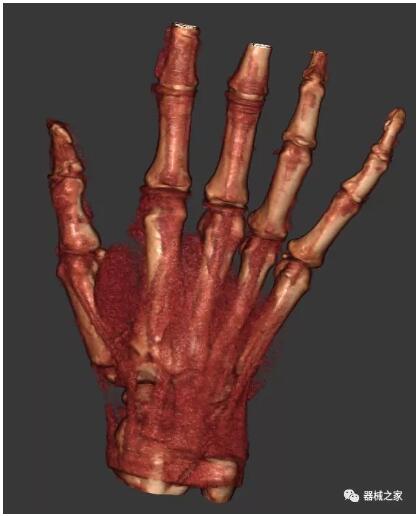

另外一款被稱為世界上最小的CT,它的重量僅300磅,不僅能夠掃查足部,還可以檢查膝蓋和上肢等。

與上面介紹的CT一樣,它同樣具有輻射低、占地空間小(23*36)的特點(diǎn),隨開隨用(支持直接接入墻上的插座)。

這款CT使用非常方便,通過上下移動保持與患者的手臂或者雙腿齊平,掃描快速,僅需要30秒左右就可以完成掃查。

以上介紹的CT均來自國外同一家公司,這些CT均配置了可視化軟件,可以進(jìn)行切片、3D重建以及大型CT附帶的所有典型的操作功能。

以下是這些“特立獨(dú)行”的CT所拍出來的圖像: